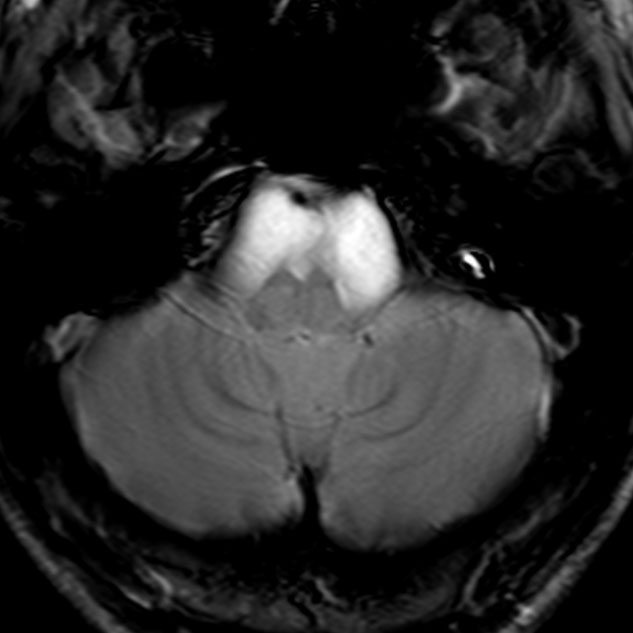

典型的な神経腸嚢胞 neurenteric cyst

左のT2強調画像で等信号,中のT2*で高信号,右はCISS画像です。

T1強調画像では,のう胞周囲の高信号の部分は半固体で,中心部の高信号はドロドロの粘液でした。基本的にガドリニウム増強はされません。まれに薄い膜状に一部が増強されることがあります。

境界明瞭は袋状の腫瘍です。椎骨動脈や脳底動脈を包み込むようにふくらんでいます。

左外側後頭下開頭という小さな開頭手術だけで全摘出しました。術後は幸い何の症状も出ていません。この例は脳幹部に食い込まないもので,運良く全摘できたのですが,そうはいかないものもあります。